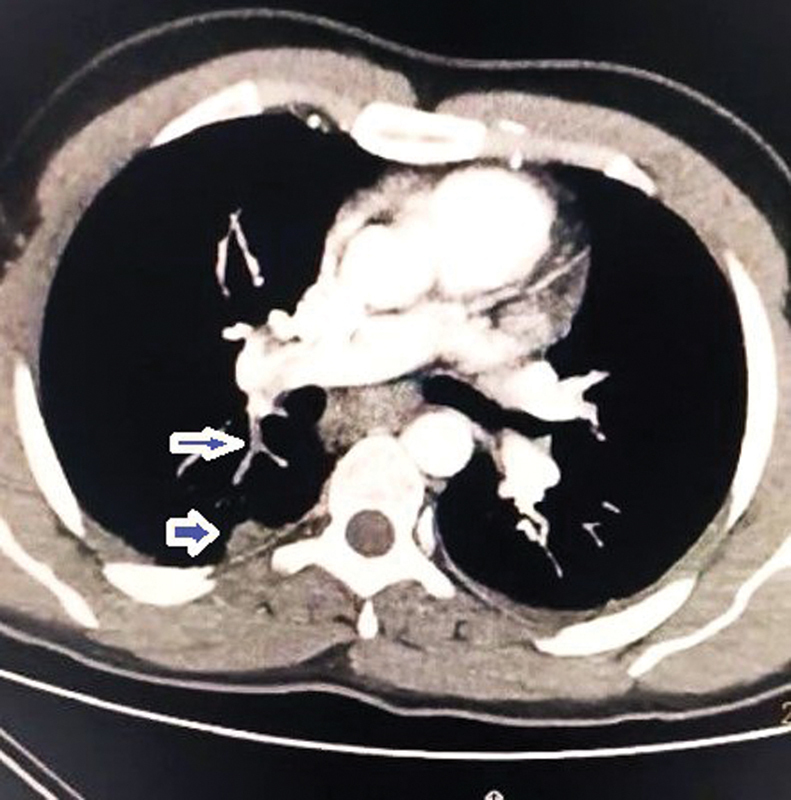

本病例报告介绍了一例中年男子,他经历了罕见和严重的水痘感染,发展为水痘肺炎和罕见的深静脉血栓形成并发症,以及随后的肺栓塞。尽管具有免疫功能,但患者的水痘感染导致了一个非典型和复杂的临床过程。患者最初表现为水疱疹、发热和疲劳,随后发展为严重缺氧和呼吸困难。影像学表现为双侧弥漫性结节实变,符合水痘肺炎。虽然水痘肺炎有很好的文献记载,但它在免疫能力强的个体中并不常见。在水痘感染的情况下,这是非常罕见的,特别是在没有免疫缺陷和没有其他危险因素的情况下,在男性患者中。该病例强调了在健康个体中保持高临床怀疑指数以及时诊断和治疗与水痘感染相关的可能危及生命的并发症的重要性。关键的学习要点包括早期识别和干预以减轻严重并发症的必要性,水痘肺炎患者可能需要血栓预防,并建议水痘肺炎患者可能需要血栓预防以预防血栓事件。

This case report presents the case of a middle-aged man who experienced a rare and severe presentation of varicella infection, with the development of varicella pneumonia and the rare complications of deep venous thrombosis, and a subsequent pulmonary embolism. Despite being immunocompetent, the patient's varicella infection resulted in an atypical and complex clinical course. The individual initially presented with a vesicopustular rash, fever, and fatigue, which progressed to severe hypoxia and dyspnea. Radiological findings revealed diffuse bilateral nodular consolidation consistent with varicella pneumonia. Although varicella pneumonia is well documented, its occurrence in immunocompetent individuals is uncommon. In the context of varicella infection, it is very rare, particularly in the absence of immunodeficiency and with no other risk factors, in a male patient. This case underscores the importance of maintaining a high index of clinical suspicion to promptly diagnose and treat potentially life-threatening complications associated with varicella infection in otherwise healthy individuals. Key learning points include the necessity of early recognition and intervention to mitigate severe complications and the potential need for thromboprophylaxis in varicella pneumonia patients and suggests the potential need for thromboprophylaxis in patients with varicella pneumonia to prevent thrombotic events.